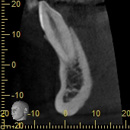

インプラント治療において、CTによる術前診断は不可欠のものとなっています。

CT画像上で、インプラントを埋入する部位の骨の幅・厚み・形態・骨質、さらには上顎洞や血管・神経との距離、上部構造の方向との関連性などを総合的に把握することにより、安全で確実な治療が可能となります。

逆に言うならば、CTによる術前診断なしのインプラント治療は危険と言わざるを得ません。さらには、術後の埋入状態や経過観察時のCT撮影が行われるならば、それに越したことはありません。

当院では、インプラント治療時には、歯科用コーンビームCT「KR―XSCAN」㈱)近畿レントゲン工業社を用いて、術前、術後および経過観察時のCT撮影を行っています。